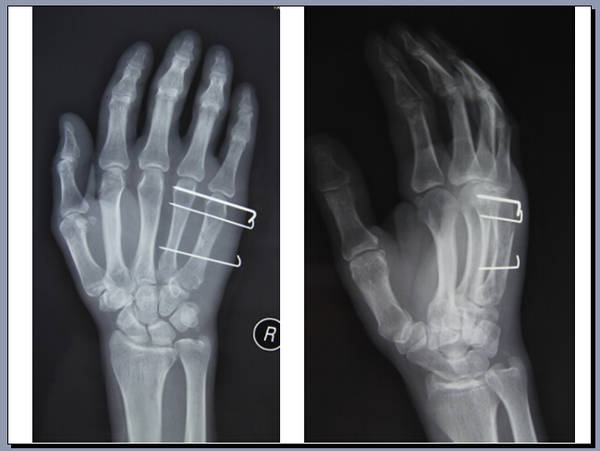

手外科会议带去一个讨论题目